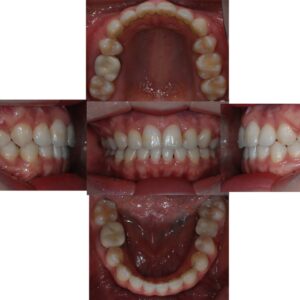

목동치아교정 🦷임플란트 & 교정시술 사례🦷

목동치아교정 🦷임플란트 & 교정시술 사례🦷 연세고운미소치과 목동점은 ‘고운미소치과 네트워크’1호점으로 2002년부터 양천구 목동에서 자리를 지켜왔습니다. · 치의학 박사 문원규 원장님 직접 진료 · 자연치아 보존한 후 최소 식립 · 치쥐료 후 건강한 잇몸에 식립 · 교정과 협진으로 식립 개수를 줄이는 노하우 · 임플란트 보증 사후 관리 시스템 과잉진료 없는 정밀한 검진, 더보기…

목동교정치과 🦷임플란트 & 교정시술 사례🦷

목동교정치과 🦷임플란트 & 교정시술 사례🦷   연세고운미소치과 목동점은 ‘고운미소치과 네트워크’1호점으로 2002년부터 양천구 목동에서 자리를 지켜왔습니다. · 치의학 박사 문원규 원장님 직접 진료 · 자연치아 보존한 후 최소 식립 · 치쥐료 후 건강한 잇몸에 식립 · 교정과 협진으로 식립 개수를 줄이는 노하우 · 임플란트 보증 사후 관리 시스템 과잉진료 없는 정밀한 더보기…